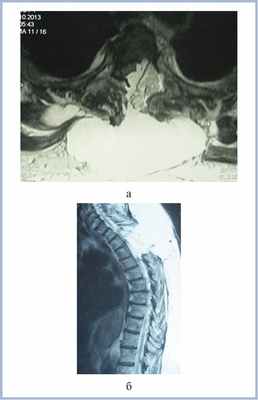

На следующий после выписки день пациентка отметила появление припухлости в области послеоперационного рубца, онемение и слабость в ногах, что послужило причиной для повторной госпитализации в стационар. В неврологическом статусе при поступлении доминирует синдром заднестолбовой атаксии (снижение вибрационной чувствительности с уровня Th5—Th6 позвонков, неустойчивость в позе Ромберга), оценка по шкале Klekamp—Samii 18 баллов. При МРТ верифицирована ликворная киста (псевдоменингоцеле) в зоне оперативного вмешательства, дислоцирующая спинной мозг кпереди (рис. 2).

Рис. 2. МР-томограммы пациентки (Т2-ВИ) с менингиомой на уровне Th3—Th4 позвонков перед второй операцией в аксиальной (а) и сагиттальной (б) проекциях. Определяется компрессия спинного мозга жировым лоскутом и ликворной кистой больших размеров.

На 10-е сутки после первой операции выполнено повторное хирургическое вмешательство — пластика дефекта ТМО лоскутом широкой фасции бедра. Произведена дополнительная герметизация ликворных пространств свободным жировым лоскутом и фибриновым клеем. В послеоперационном периоде синдром заднестолбовой атаксии частично регрессировал, при этом пациентка ходила с опорой на ходунки. На 20-е сутки после удаления опухоли и 10-е сутки после герметизации ликворных пространств отмечено усугубление неврологической симптоматики в виде нарастания слабости в нижних конечностях (до 4 баллов в левой ноге и до 3 баллов — в правой), увеличение размеров ликворной кисты в области оперативного вмешательства. При контрольной МРТ верифицировано увеличение размеров ликворной кисты с дислокацией спинного мозга (рис. 3).